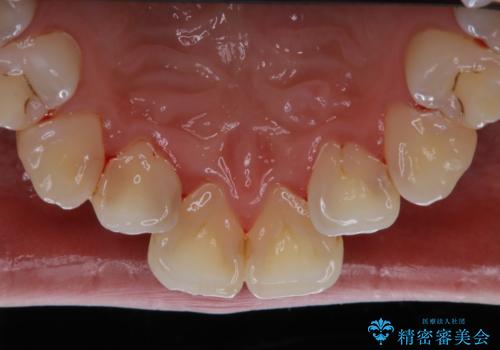

歯面がバイオフィルム(細菌の塊)や歯石で覆われていました。

PMTC(自費クリーニング)で、専門的な器具を使用し、歯石を砕き、バイオフィルムを剥がし、トリートメントまで行いました。歯肉が腫れていたため、バイオフィルムや歯石を取り除いたことにより、施術後の歯肉から出血が見られます。ただし、出血は次第におさまります。

PMTC(自費クリーニング)はホワイトニングではないため、歯が白くなることはありませんが、徹底的に汚れを除去しますので、ご自身本来の歯面となり、艶がでて明るい印象となります。